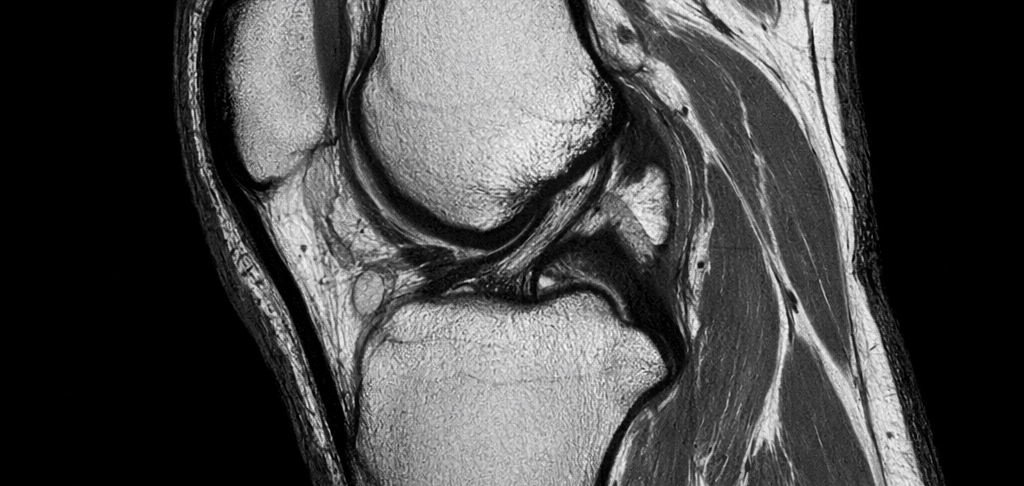

Examens complémentaires

Certains examens peuvent être prescrits :

échographie du genou

radiographie

IRM du genou

Ces examens permettent d’identifier la cause de la douleur.